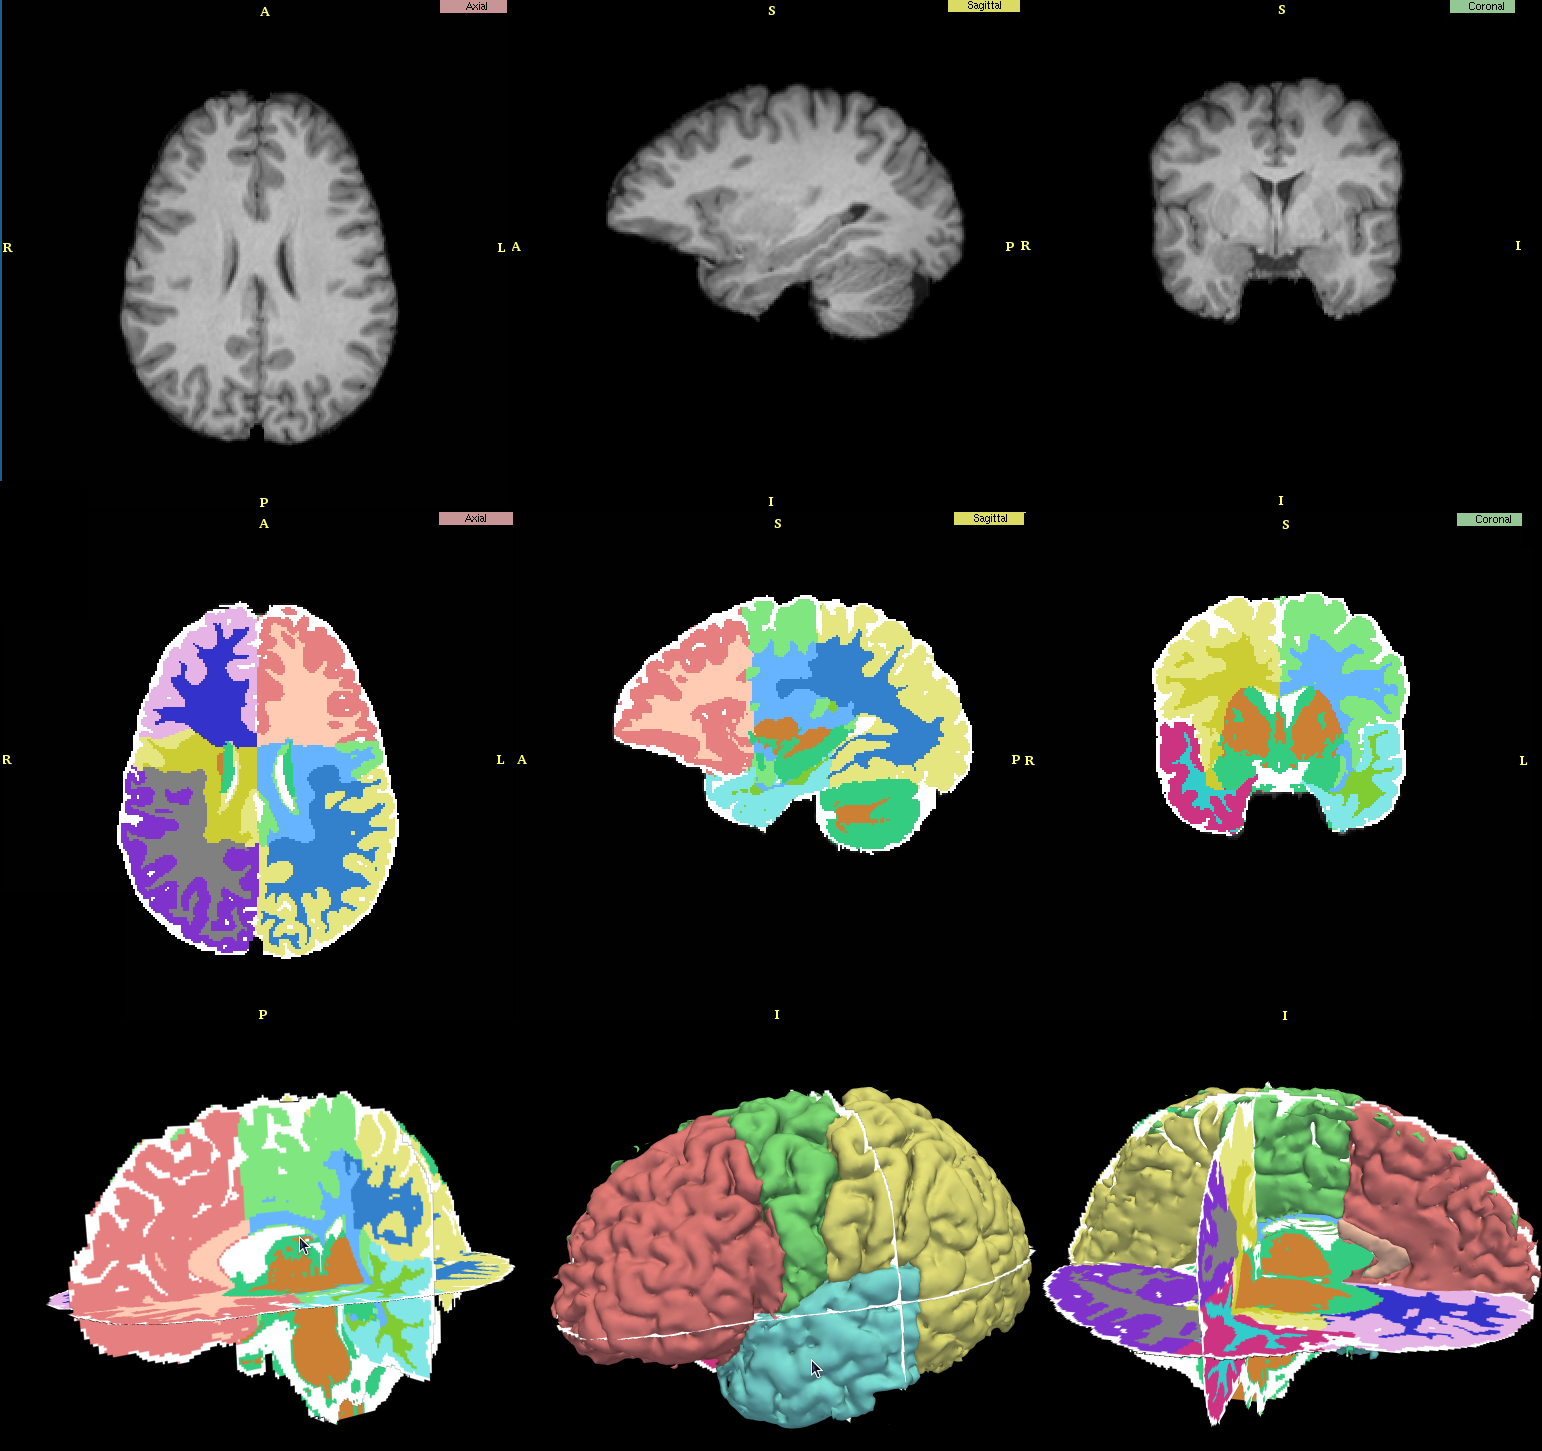

3d Slicer Automatic Segmentation

3dslicer Wikiwand